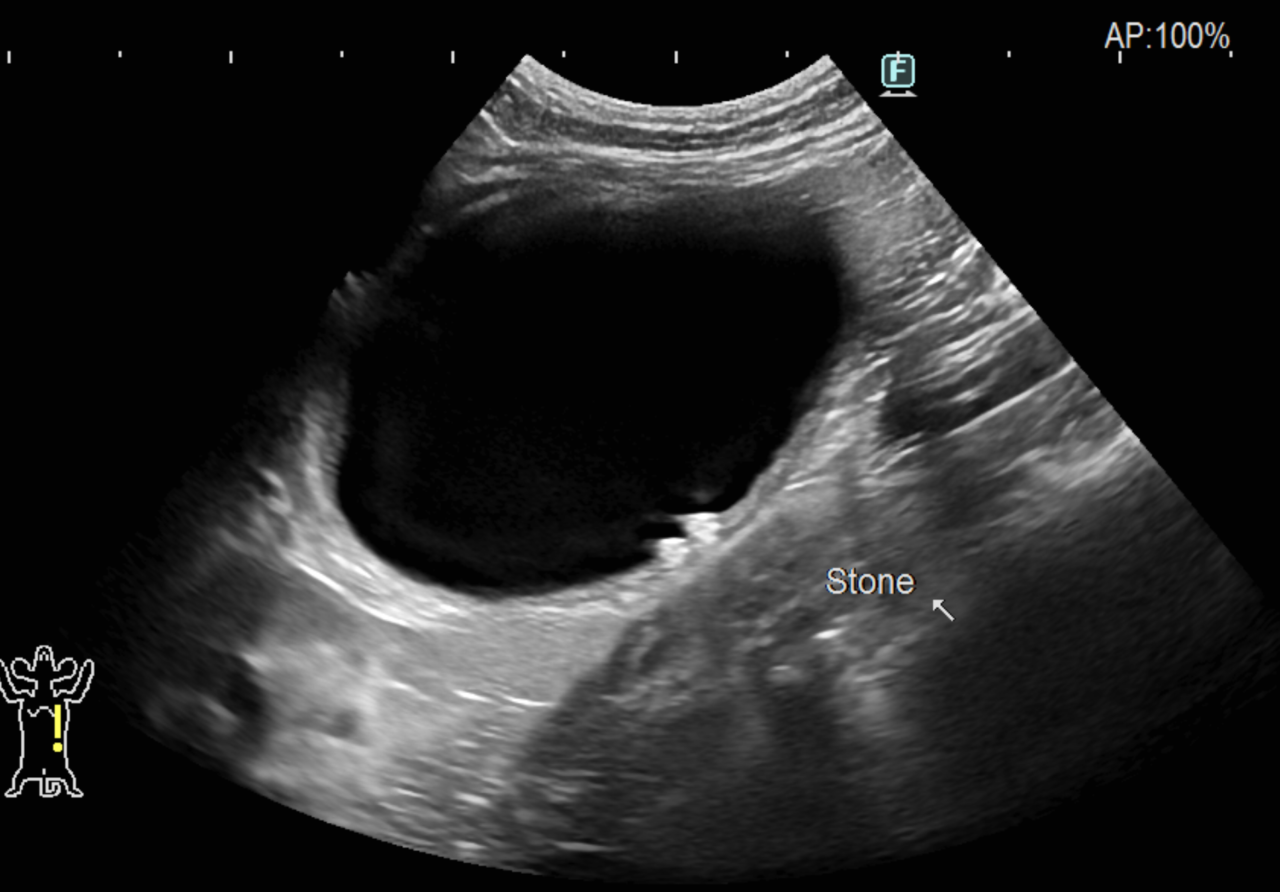

15歳のオス猫さんが尿道結石により何度か尿道閉塞を繰り返しており、内科的な管理の限界ではないかと主治医の先生から尿路解放術の依頼がありました。閉塞した尿道結石を摘除し、包皮粘膜を利用した尿道瘻(尿道を太くする手術)を設置しました。”猫が尿毒症になるまでオシッコを出せなくて苦しむ”という場面は想像もしたくありませんが。またシュウ酸Ca結石は基本的に溶解することは期待できません。これからは気持ちよく、たくさんオシッコをしてもらいたいです。高齢ながら頑張ってくれました。